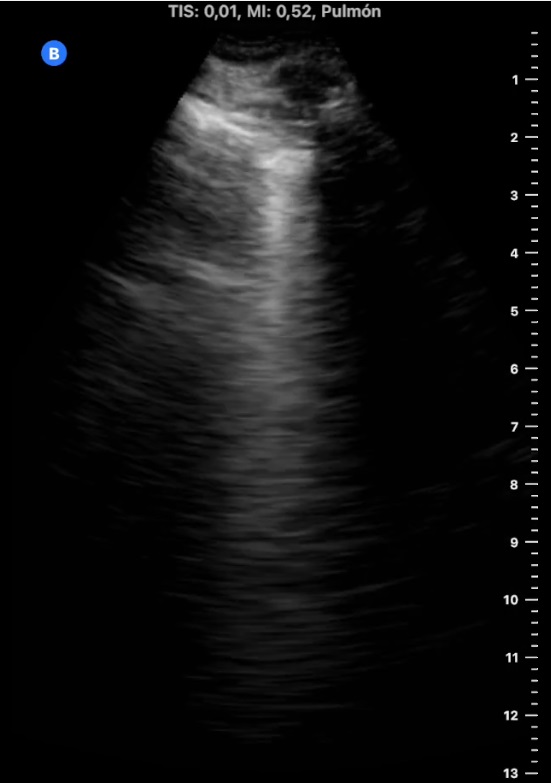

Ecografía pulmonar en AP:

«Líneas B en campos pulmonares izquierdos y consolidación pulmonar en base derecha con mínimo derrame pleural, compatible consolidación infecciosa vs tromboembólica.

Se amplía estudio con ETT que no muestra signos de sobrecarga de ventrículo derecho, y eco Doppler de MMII sin hallazgos de TVP con venas safenas y femorales permeables y colapsables».